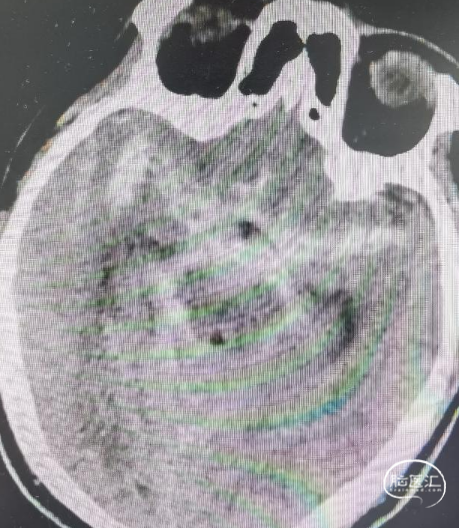

术前影像

CT显示广泛蛛网膜下腔出血,右侧侧裂池为著。